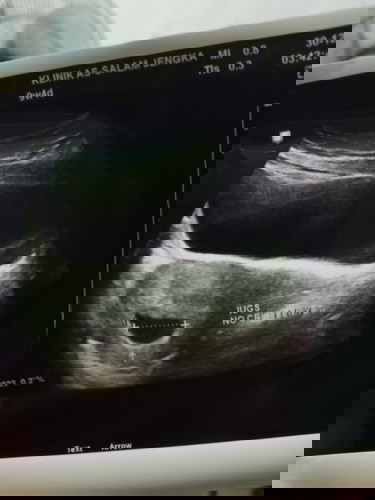

Hi , nak tnya kantong macam ni tak bulat normal ke? Ada tak ibu" yang pernah mengalami macam ni ? Sbb sy tgh spotting dah 4hari. Gi scan doc kata kantung tak comel. #ingintahu #firstbaby #pleasehelp #bantusharing #seriusnanya

macam saya gugur haritu,sebiji lah scan ikut bawah bentk mcm ni,selang 2-3 terus jatuh/gugut